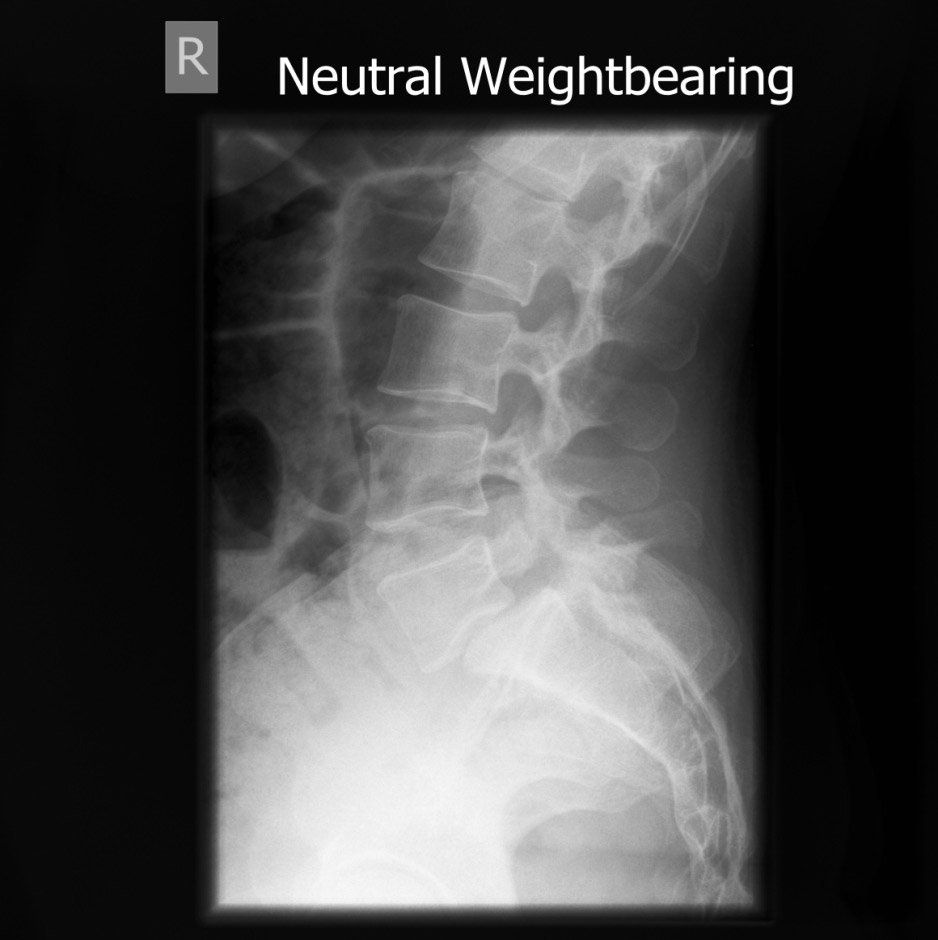

The images show how I treat a stress fracture of the lowest bone in the spine.

On this CT. The bones to the right of the image lie on top of each like roof tiles. The roof tile is disrupted in the lowest image because of a fracture (i.e a broken bone)

The disc space is seen to be distorted and the lower bone has changed to a white colour which can be a sign that this is causing pain.

This is the before surgery X-ray showing that the lowest bone has slipped forward.